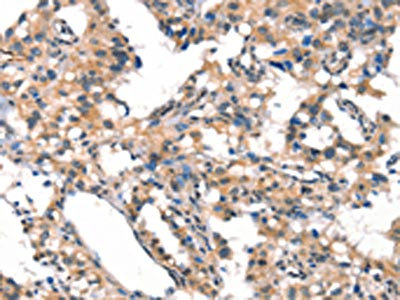

The image on the left is immunohistochemistry of paraffin-embedded Human thyroid cancer tissue using CSB-PA051152(CYP2D6 Antibody) at dilution 1/30, on the right is treated with synthetic peptide. (Original magnification: ×200)